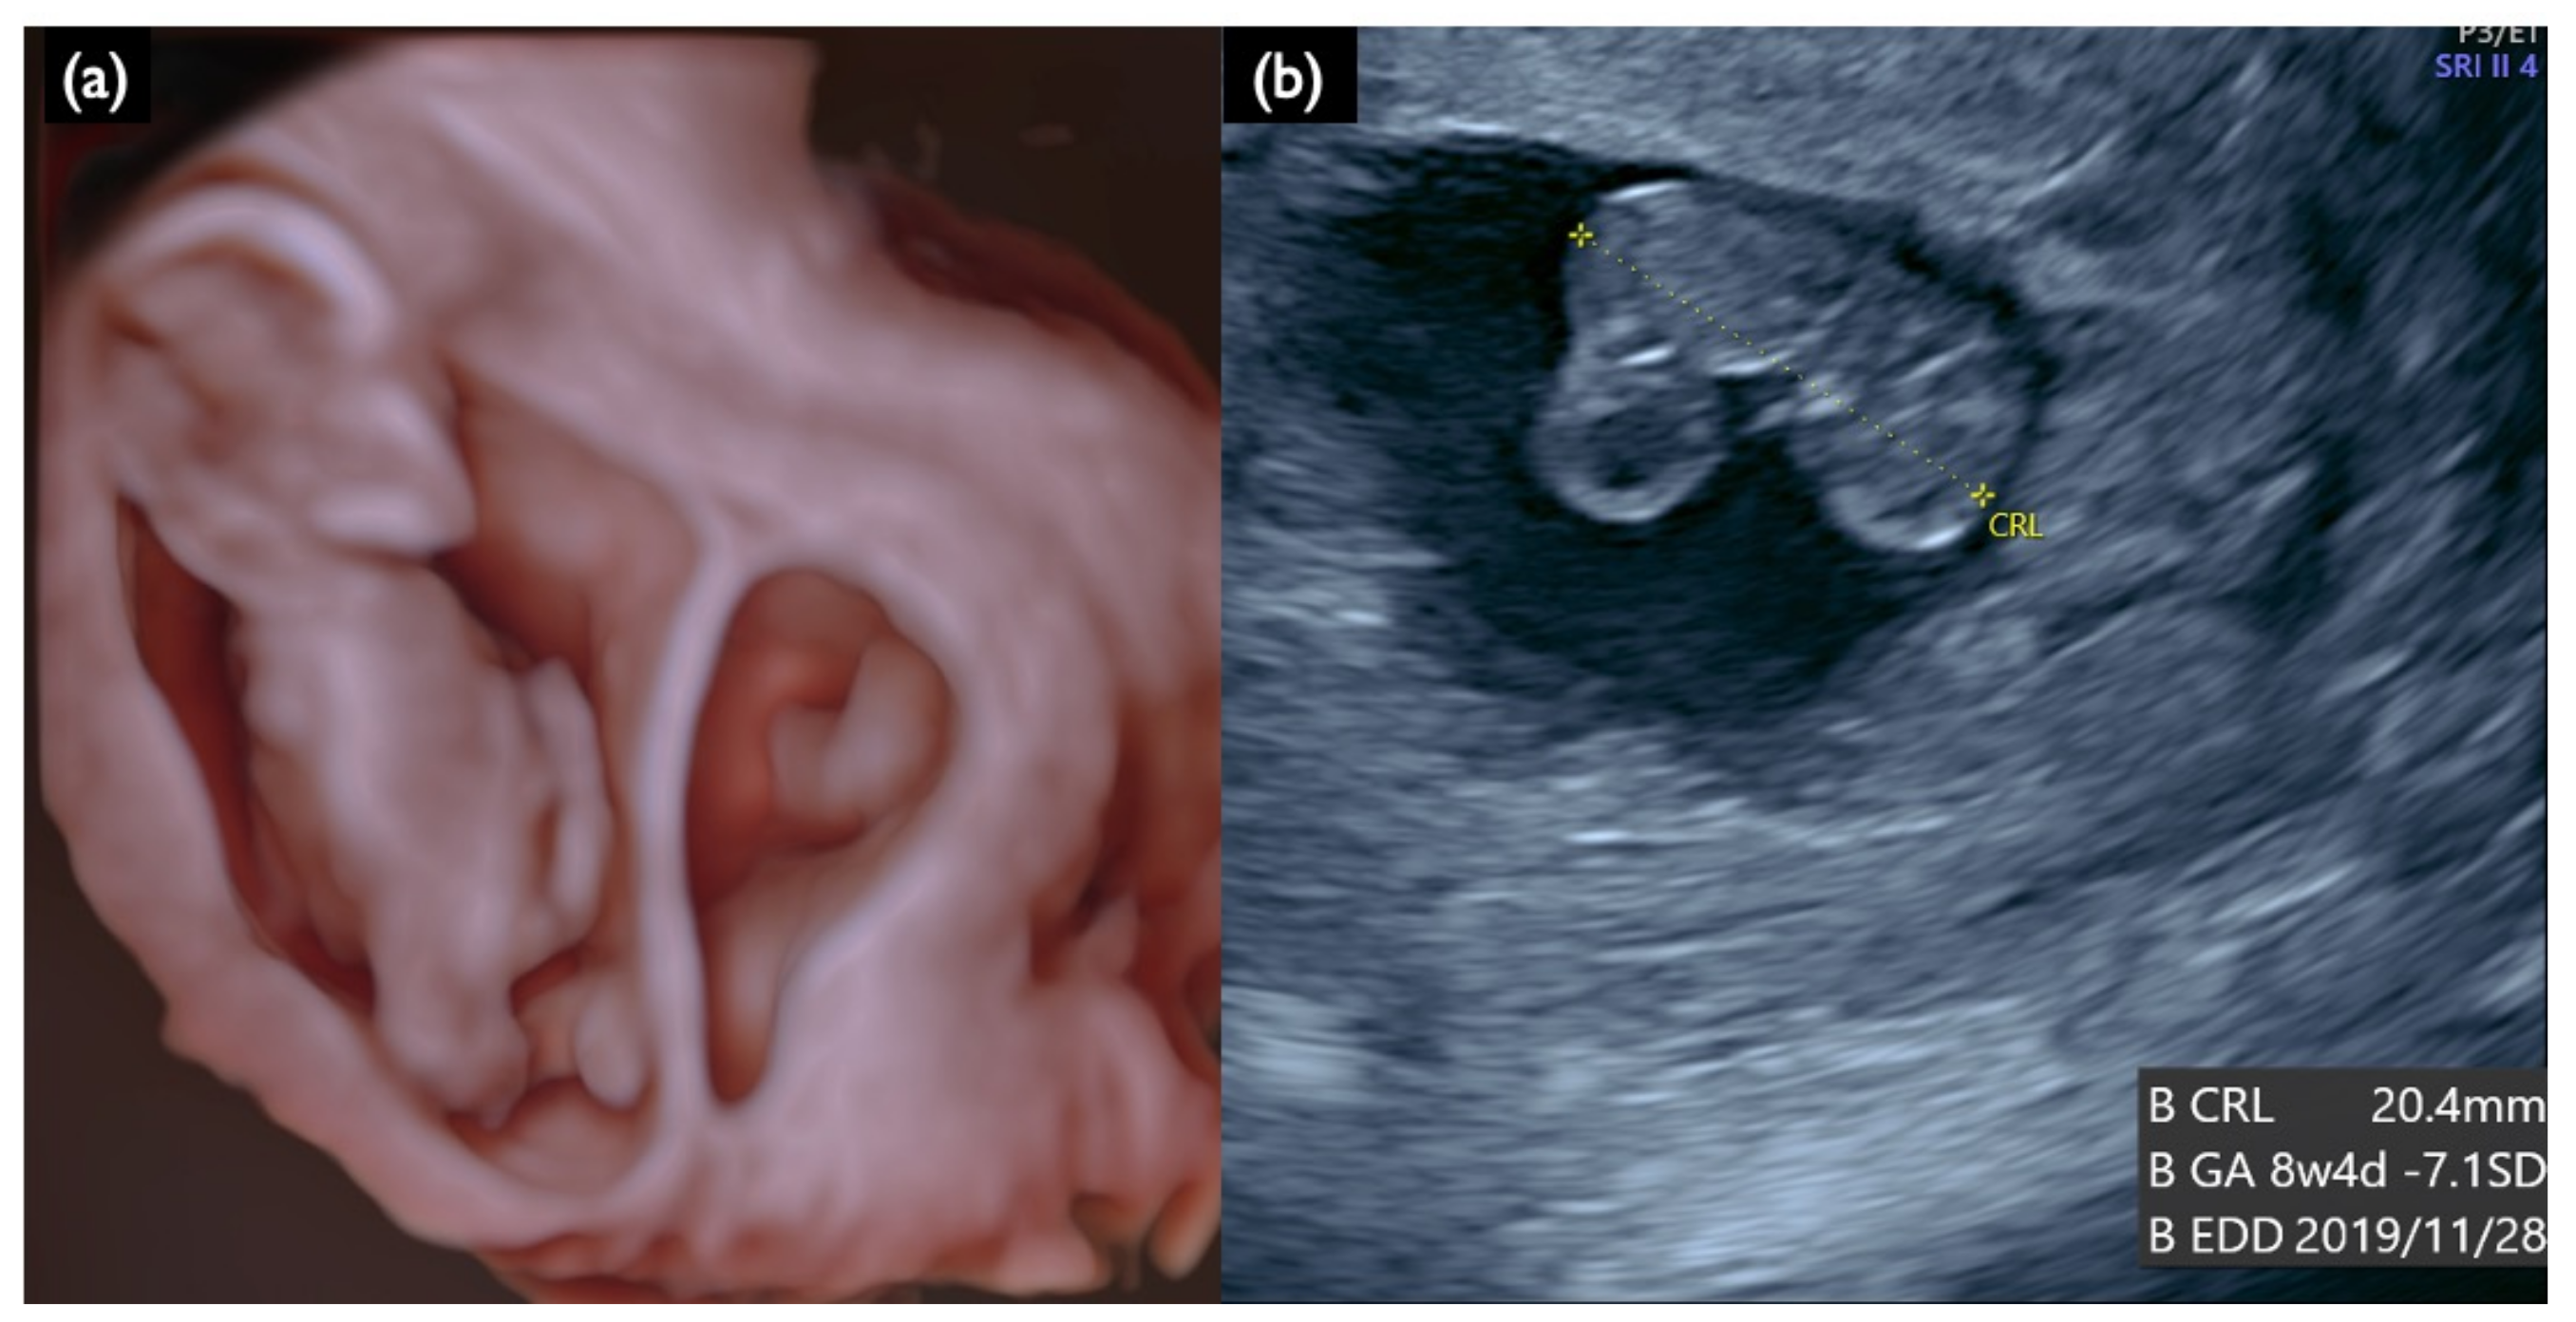

| FN1 | 47,XY,+21 | T21 negative | 1.07 | – | – | – | – | – | – | – | – | 46,XX | unclear | + | 7.2 | Increased NT, GE mild, NB defect, Lowset ear, TR mild, Small stomach, DV reverse, Tachycardia, T21 is strongly suspected |